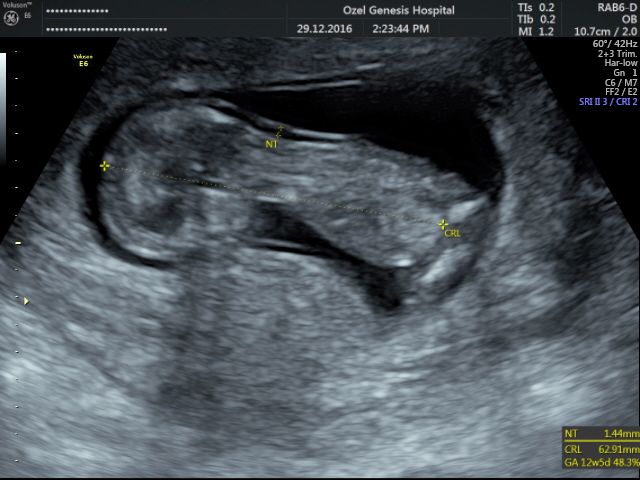

Merhaba , nub teorisine göre cinsiyet tahmini yapan arkadaşımızın dediği gibi resimlerinizin net olması gerekmektedir. Doktorunuz çekim anında görüntüyü net olarak görebilmektedir. Elinize verilen görsel doktorun verdiği görüntü kadar net olmayabilir..Durumu değerlendirilen arkadaşların yolladığı gibi lütfen görselleriniz net olsun.